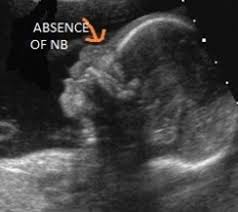

Three Dimensional Ultrasound With Maximal Mode Rendering A Novel Technique For The Diagnosis Of Bilateral Or Unilateral Absence Or Hypoplasia Of Nasal Bones In Second Trimester Screening For Down Syndrome Benoit 2005

Short Nasal Bone

Do Babies With Down S Syndrome Have No Nose Bone Babycentre Uk

Fetal Nasal Bone Hypoplasia In The Second Trimester And Risk Of Abnormal Karyotype In A Population